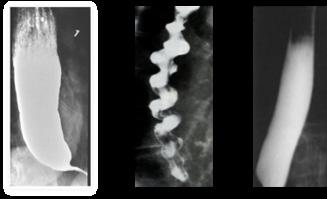

4 (ENAM 2017)

A continuación, se debe reconocer si el ritmo es desfibrilable, lo cual incluye la fibrilación ventricular y taquicardia ventricular sin pulso , donde se procede como sigue:

Energía de descarga eléctrica: 360 joule si es monofásico o 200 joule si es bifásico en adultos; 2 joule/kg la primera y luego 4 joule/kg las siguientes en pacientes pediátricos.

Figura 58. Colocación de palas para desfibrilación o cardioversión eléctrica. la paleta esternal se coloca a la derecha del esternón, justo debajo de la clavícula derecha en la línea medioclavicular. La paleta apical se coloca en 5 espacio intercostal izquierdo, con la línea axilar media o anterior, que corresponde a la posición de la punta del corazón.

Los desfibriladores bifásicos tienen una mayor tasa de éxito si utilizan una corriente más baja, lo que causa menos daño al tejido cardíaco. Primera descarga: 120-200 J Choques adicionales: 200–360 J